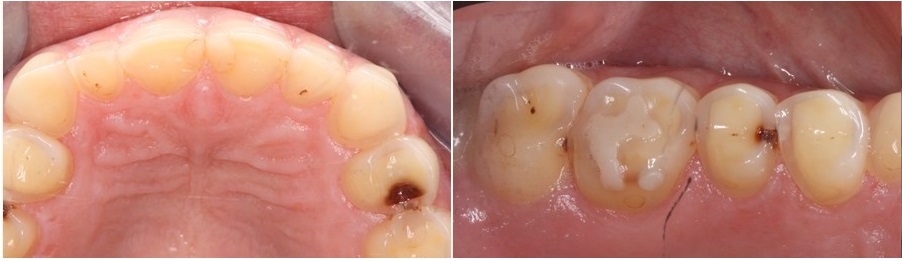

Στην διάβρωση των δοντιών οι περιοχές στις οποίες εντοπίζεται αρχικά το πρόβλημα είναι οι υπερώιες πλευρές των άνω πρόσθιων δοντιών (φωτογραφία αριστερά). Στα πρώιμα στάδια η βλάβη είναι πολύ δύσκολα αναγνωρίσιμη λόγω του ότι η θέση των δοντιών αυτών δεν είναι εύκολα ορατή στον ασθενή. Σιγά σιγά όμως η απώλεια οδοντικής ουσίας επεκτείνεται και στο κοπτικό χείλος των δοντιών τα οποία λεπταίνουν και κονταίνουν.

Στα προχωρημένα στάδια της νόσου εμφανίζονται αλλαγές και στα πίσω δόντια (φωτογραφία δεξιά) τα οποία καθώς διαβρώνονται μικραίνουν σε μέγεθος οδηγώντας τελικά σε απώλεια της κάθετης διάστασης του προσώπου. Χαρακτηριστικά σε αυτές τις περιπτώσεις τα σφραγίσματα που τυχόν υπάρχουν στα δόντια επειδή δεν διαβρώνονται, μένουν πιο ψηλά στην επιφάνεια των δοντιών ενώ η οδοντική ουσία γύρω από αυτά μειώνεται.